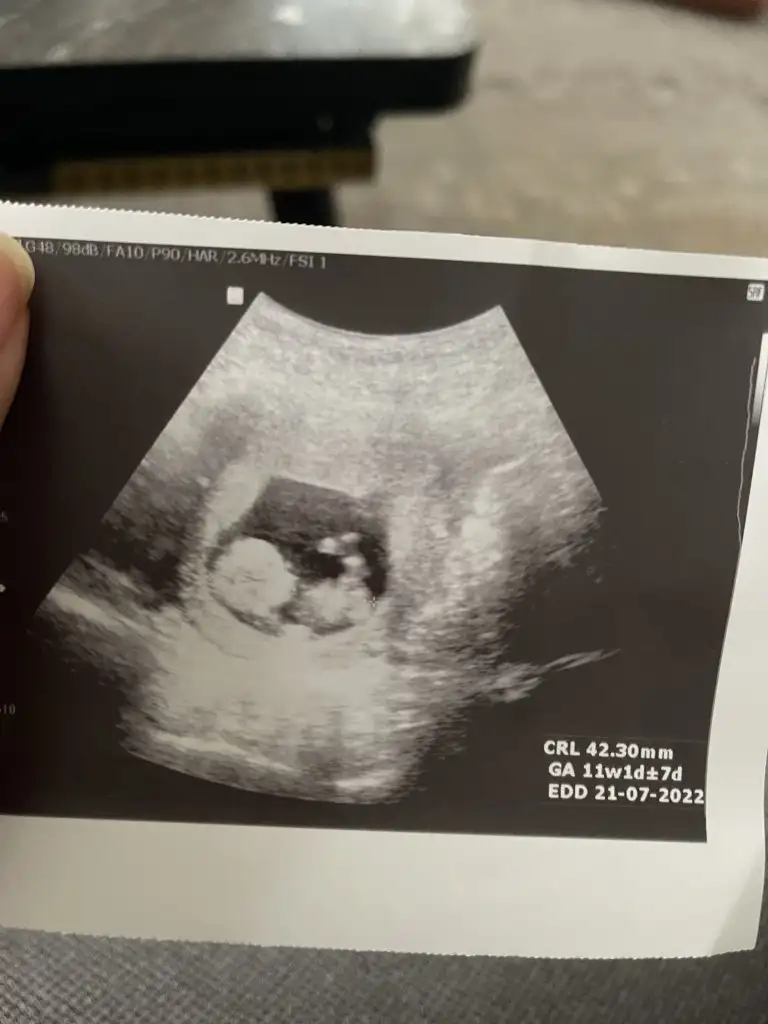

Kiz gibi sanki emin olamadımEki Görüntüle 2977845 İkra Meyra bizede bakabilir misin 12+4

Kız görünüyorCinsiyete bakabilir misinIkra meyra 11+4 günlük sizce ne olabilir l

TeşekkürlerKız görünüyor